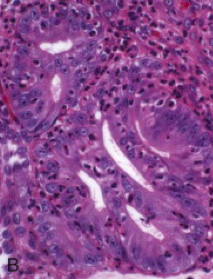

What do you see in this esophageal biopsy?

What do you see in this esophageal biopsy? Arrow?

What is going on in this esophageal biopsy?